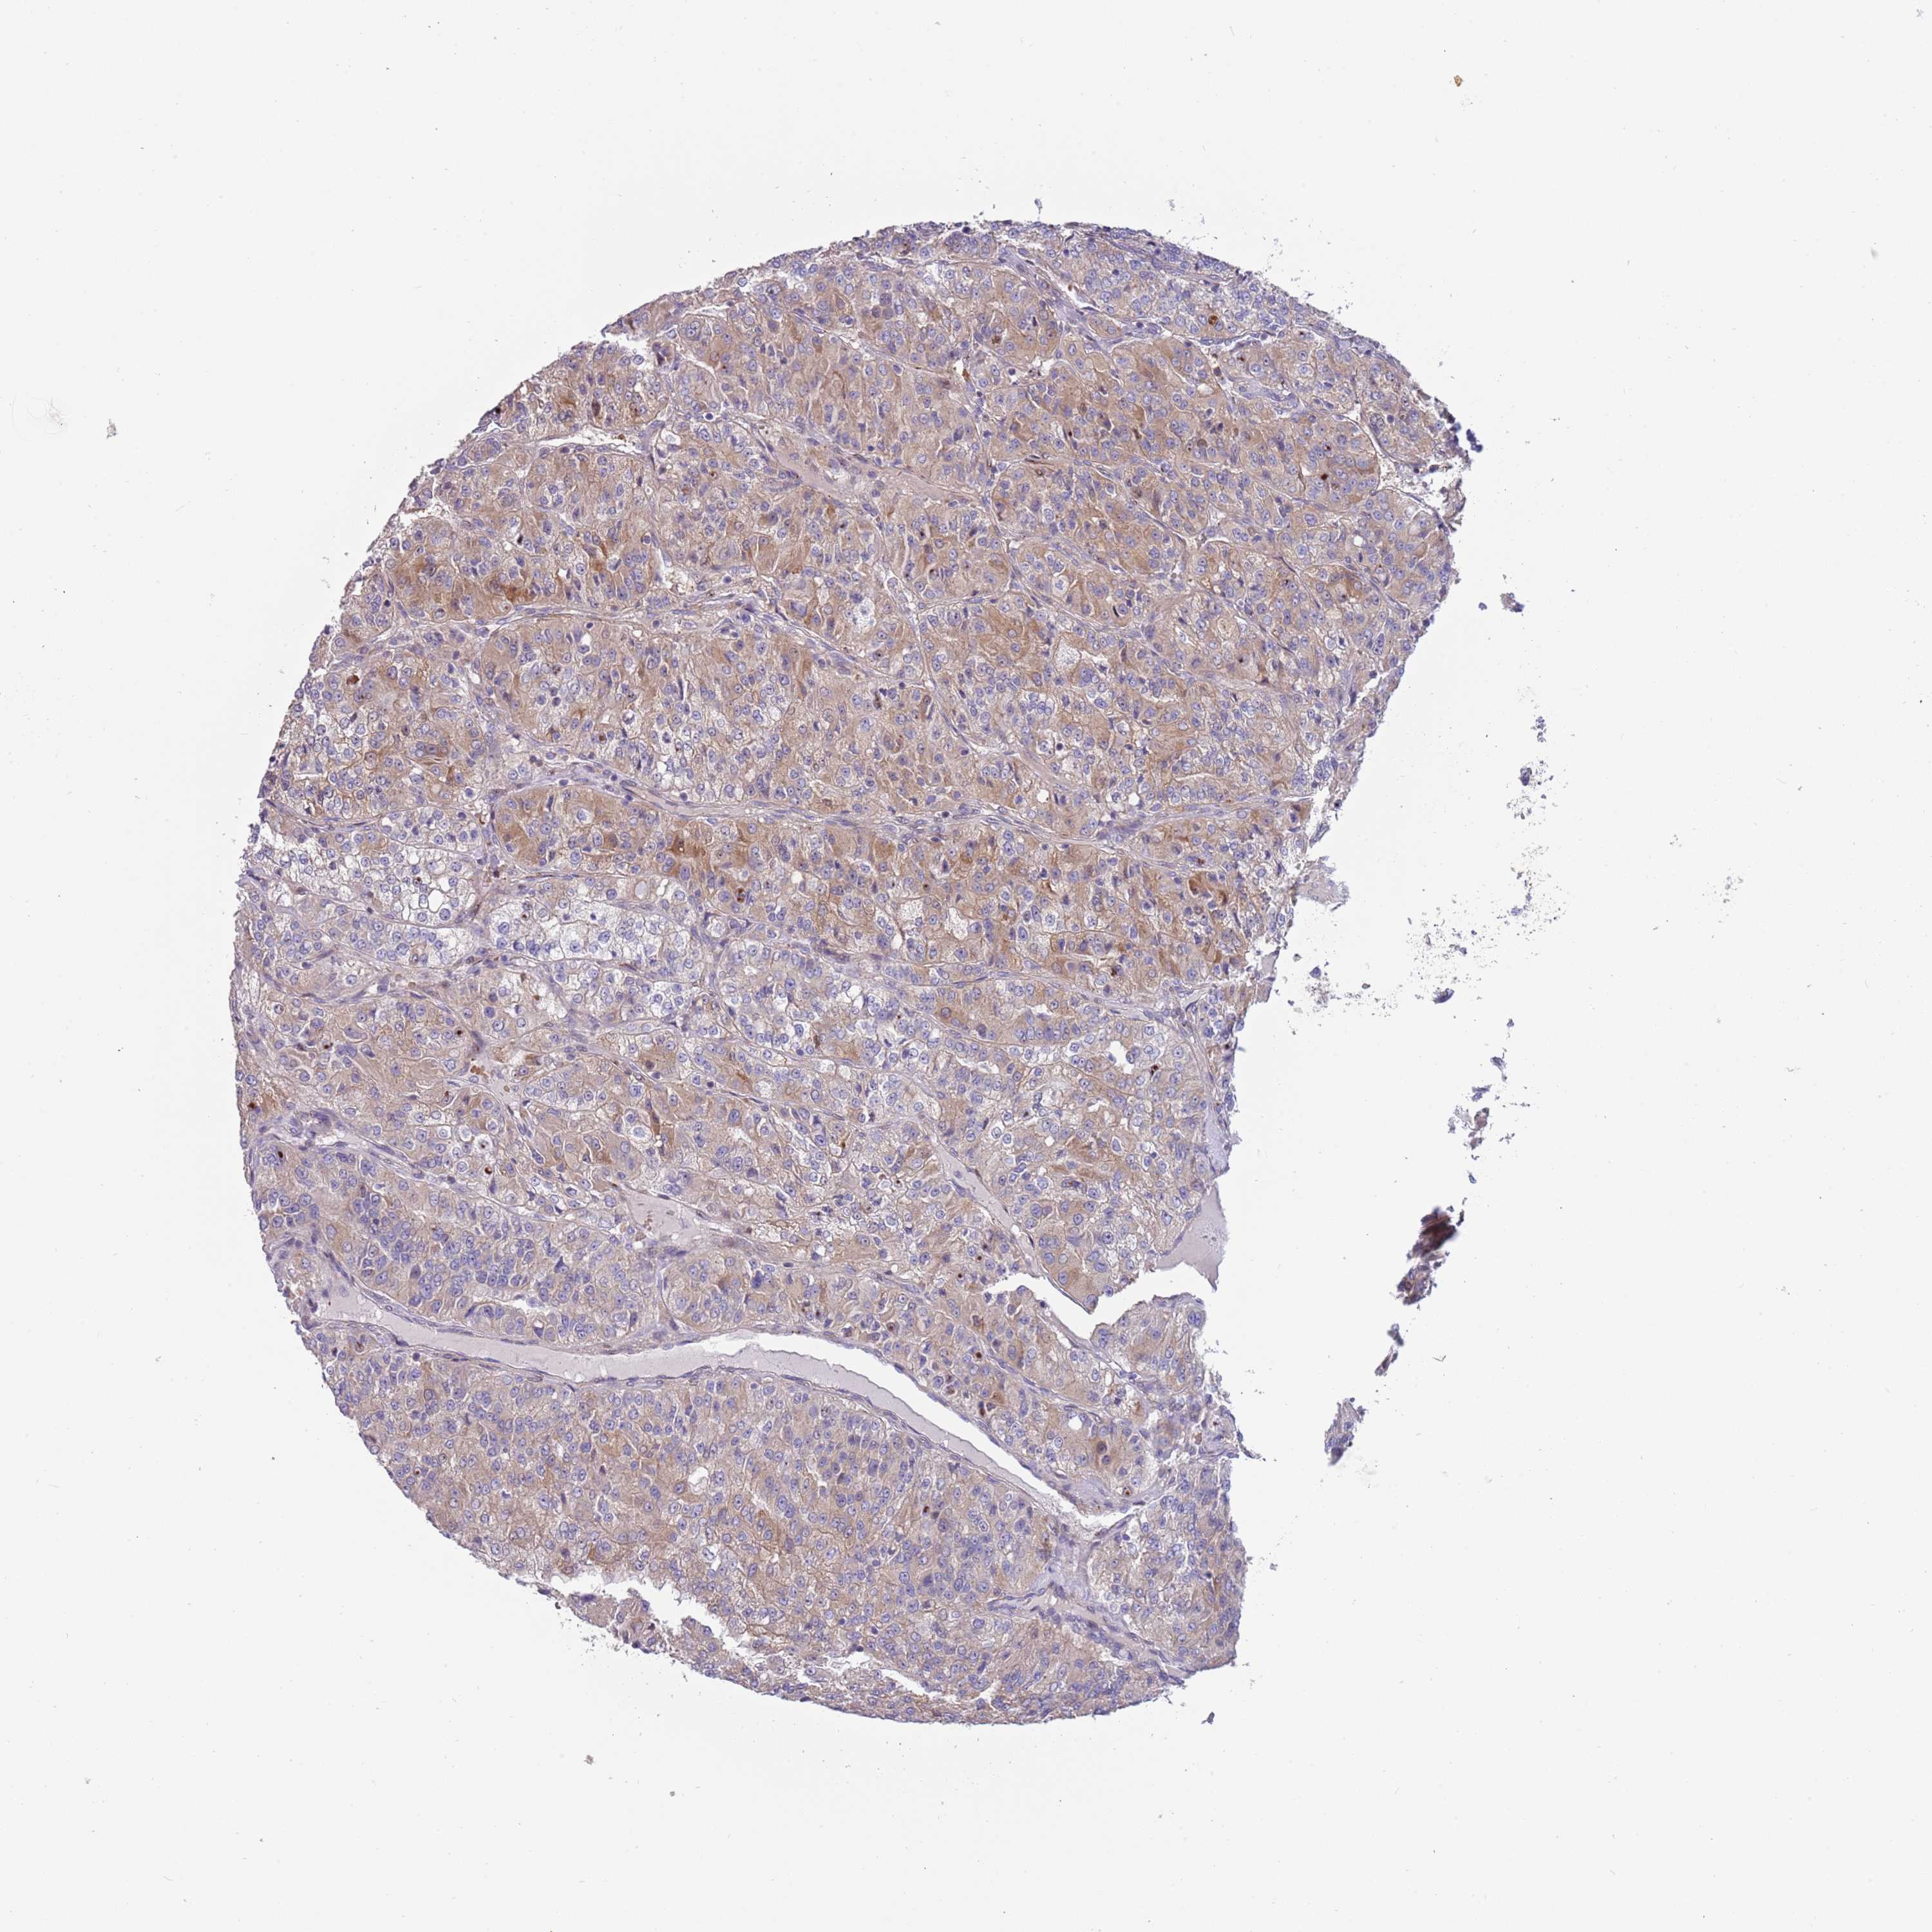

KIDNEY RENAL CLEAR CELL CARCINOMA (VALIDATION) - Interactive survival scatter ploti

The Survival Scatter plot shows the clinical status (i.e. dead or alive) for all individuals in the patient cohort, based on the same data that underlies the corresponding Kaplan-Meier plots. Patients that are alive at last time for follow-up are shown in blue and patients who have died during the study are shown in red.

The x-axis shows the expression levels (FPKM) of the investigated gene in the tumor tissue at the time of diagnosis. The y-axis shows the follow-up time after diagnosis (years). Both axes are complimented with kernel density curves demonstrating the data density over the axes. The top density plot shows the expression levels (FPKM) distribution among dead (red) and alive patients (blue). The right density plot shows the data density of the survived years of dead patients with high and low expression levels respectively, stratified using the cutoff indicated by the vertical dashed line through the Survival Scatter plot. This cutoff is automatically defined based on the FPKM cutoff that minimizes the p-score. The cutoff can be changed by dragging the vertical line or by entering a cutoff value in the square labeled "Current cut-off".

Under the Survival Scatter plot the p-score landscape (black curve; left axis) is shown together with dead median separation (red curve; right axis). Dead median separation is the difference in median mRNA expression between patients who have died with high and low expression, respectively. It is calculated as follows: median FPKM expression of dead patients with high expression - median FPKM expression of dead patients with low expression. This is intended to aid the user in visually exploring custom cutoffs and the associated p-scores and dead median separation.

Individual patient data is displayed and can be filtered by clicking on one or more of the category buttons on the top of the page. Categories describing expression level and patient information include: high, low, alive, dead, female, male and tumor stages. The scale of the x-axis can be toggled between linear and log-scale by clicking on the "x log" button. Mouse-over function shows TCGA ID, patient information and mRNA expression (FPKM) for each patient.

& Survival analysisi

Kaplan-Meier plots summarize results from analysis of correlation between mRNA expression level and patient survival. Patients were divided based on level of expression into one of the two groups "low" (under cut off) or "high" (over cut off). X-axis shows time for survival (years) and y-axis shows the probability of survival, where 1.0 corresponds to 100 percent.

ITGB6 is not prognostic in Kidney Renal Clear Cell Carcinoma (validation)

Best expression cut offi

Based on the FPKM value of each gene, patients were classified into two groups and association between prognosis (survival) and gene expression (FPKM) was examined. The best expression cut-off refers the FPKM value that yields maximal difference with regard to survival between the two groups at the lowest log-rank P-value. Best expression cut-off was selected based on survival analysis .

When clicking on this number, the vertical dashed line indicating cut-off, the interactive survival plot, and the Kaplan-Meier curve will be adjusted to show results based on the best expression cut-off.

: 10.82

P scorei

Log-rank P value for Kaplan-Meier plot showing results from analysis of correlation between mRNA expression level and patient survival.

N/A

TCGA RNA samplesi

RNA-seq data is reported as average FPKM (number Fragments Per Kilobase of exon per Million reads), generated by the The Cancer Genome Atlas (TCGA) .

Normal distribution across the dataset is visualized with box plots, shown as median and 25th and 75th percentiles. Points are displayed as outliers if they are above or below 1.5 times the interquartile range. FPKM values of the individual samples are presented next to the box plot.

Average pTPM 8.4

Number of samples 100